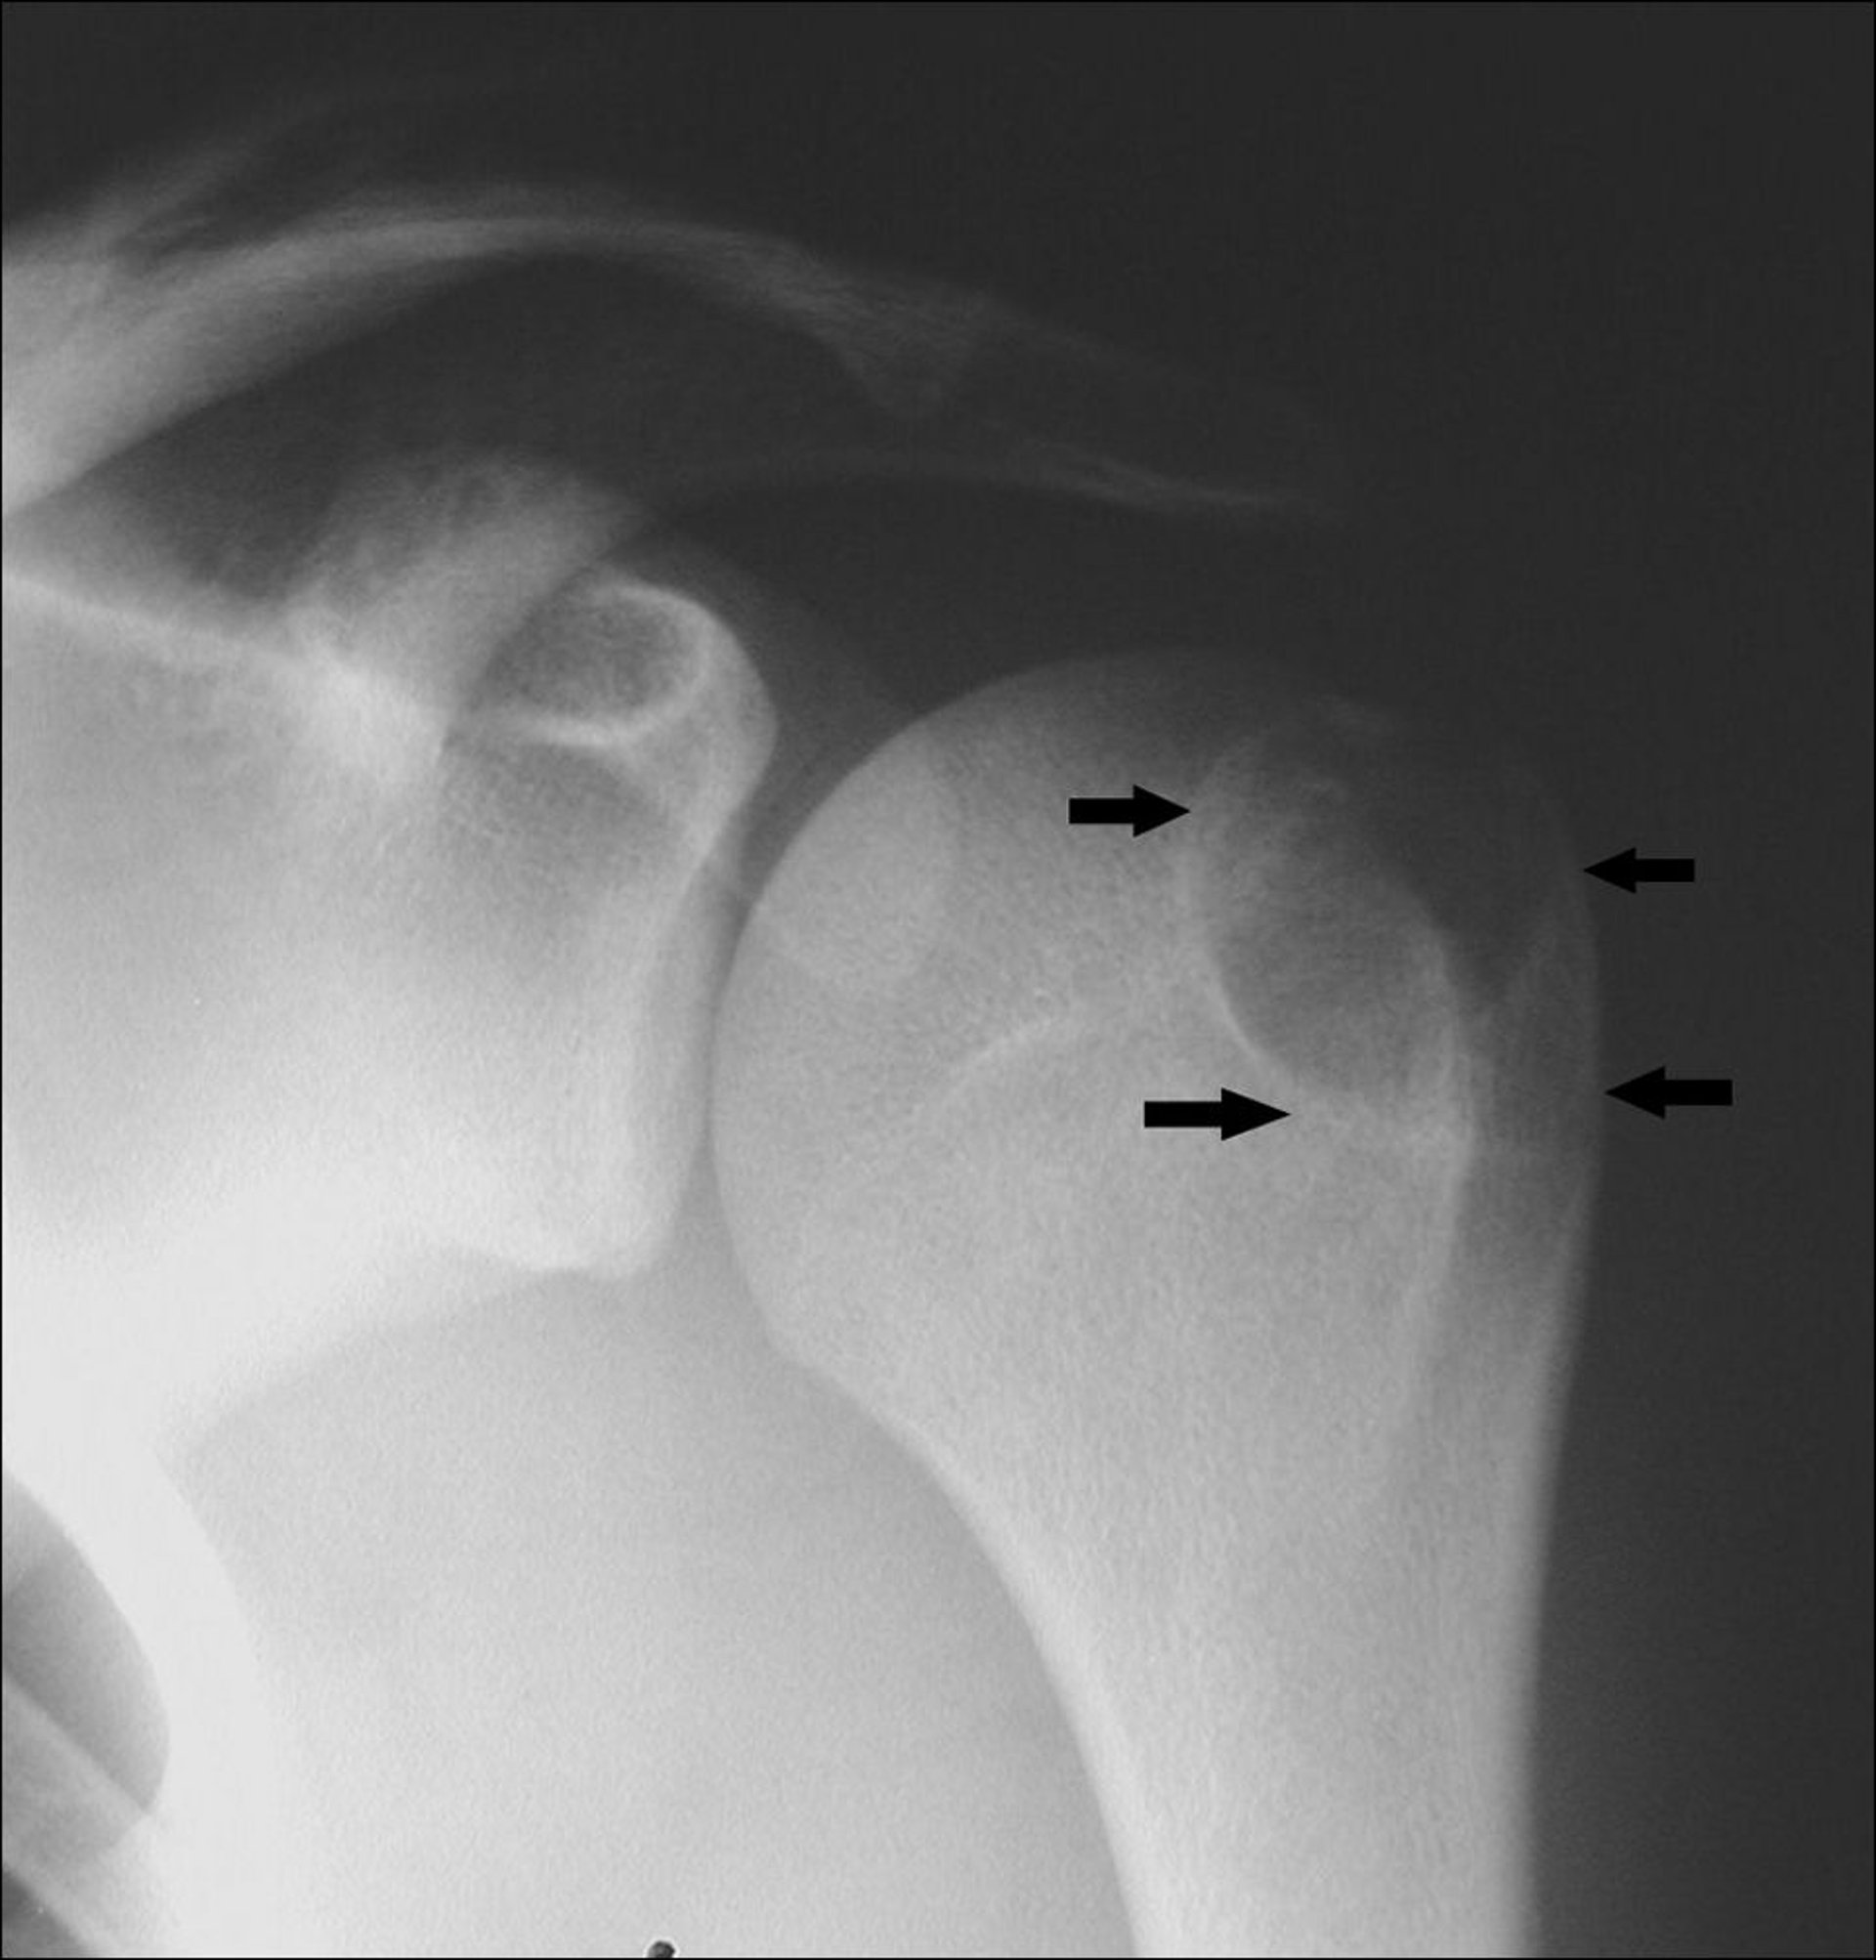

Chondroblastome

Cette radiographie de l’épaule montre un chondroblastome au bout de l’os de l’avant-bras (flèches).

Image publiée avec l’aimable autorisation des Drs Michael J. Joyce et Hakan Ilaslan.